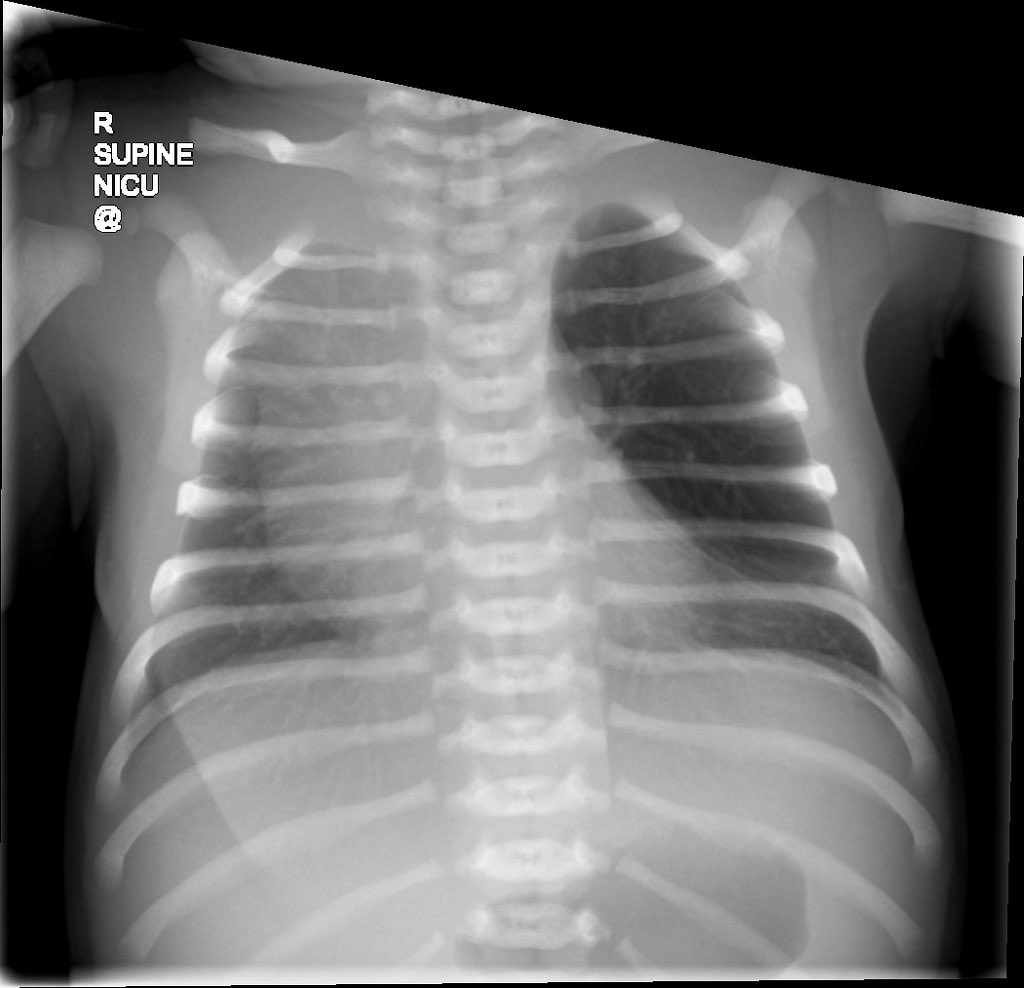

Scroll through the images in this quiz case on @Radiopaedia: radiopaedia.org/cases/d7151fa3… How many hernias can you see? I'll share the answer over the weekend! #FOAMrad